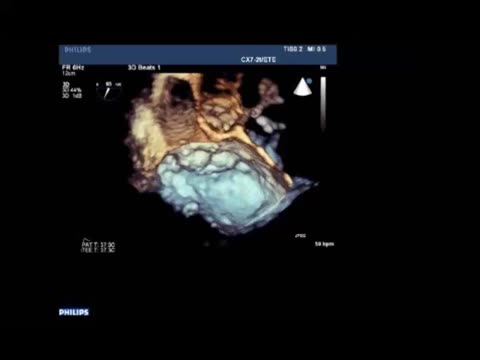

The initial plan was to implant a 23-mm CoreValve Evolut R (Medtronic, Irvine, CA) in aortic position (transfemoral approach) and a 29-mm Edwards SAPIEN 3 in mitral position (transapical approach). The procedure began with a successful left transfemoral approach with a 14-F Fast-Cath sheath, and the left coronary artery was protected with an angioplasty guidewire. Due to extreme difficulty in retrograde crossing of the aorta, a transapical-transfemoral loop approach was considered. The loop was created after gaining transapical access (Figure 2A), through which an INFINITI MPA 2 catheter (5.0 Fr×125 cm, Cordis) was used to advance an Emerald J wire (0.035″×260 cm) anterogradely until it reached the left common iliac artery, where it was captured with a 25-mm Amplatz Goose Neck snare (Figure 2B). After wire externalization at the left groin, the MPA 2 catheter was removed from the apical access and inserted via the groin, enabling the Emerald J wire to be exchanged for an Amplatz Extra Stiff guidewire (0.035″×260 cm) via a left transfemoral route (Video 2). The CoreValve was then successfully advanced into the aortic root and implanted in a suprannular aortic position under rapid pacing (Figure 2C and Video 3), 7 mm below the radiopaque Mitroflow ring. The left coronary ostium was unobstructed. Subsequently, the mitral valve-in-valve Edwards was successfully implanted transapically, without complications (Figure 2D and Video 4). Intraprocedural transesophageal echocardiography showed normal gradients (mean aortic gradient 11 mmHg, mean mitral gradient 3 mmHg) (Figure 2E and F) and a mild aortic perivalvular leak (Video 5). There were no immediate procedural complications. Due to contrast nephropathy and development of anuria (serum creatinine increased to 5.1 g/dl), the patient needed temporary renal replacement therapy, which was discontinued after two and a half weeks due to resumed diuresis. Before discharge, TTE revealed a small paravalvular aortic leak and normally functioning prosthetic valves. The patient was discharged in New York Heart Association (NYHA) functional class II on the 67th day with mild anemia (hemoglobin 11.5 g/dl), creatinine 1.0 mg/dl and eGFR 30 ml/min/1.73 m2.

(A) A long Emerald J wire passes through the stenotic Mitroflow, in which it is captured with an Amplatz Goose Neck snare (B); valve-in-valve implantation of a 23-mm CoreValve Evolut R in aortic position by the transfemoral route (C); implantation of a 29-mm Edwards SAPIEN 3 in mitral position by the transapical route (D); new aortic (E) and mitral (F) bioprosthetic valves visualized by transesophageal echocardiography during the procedure following implantation.